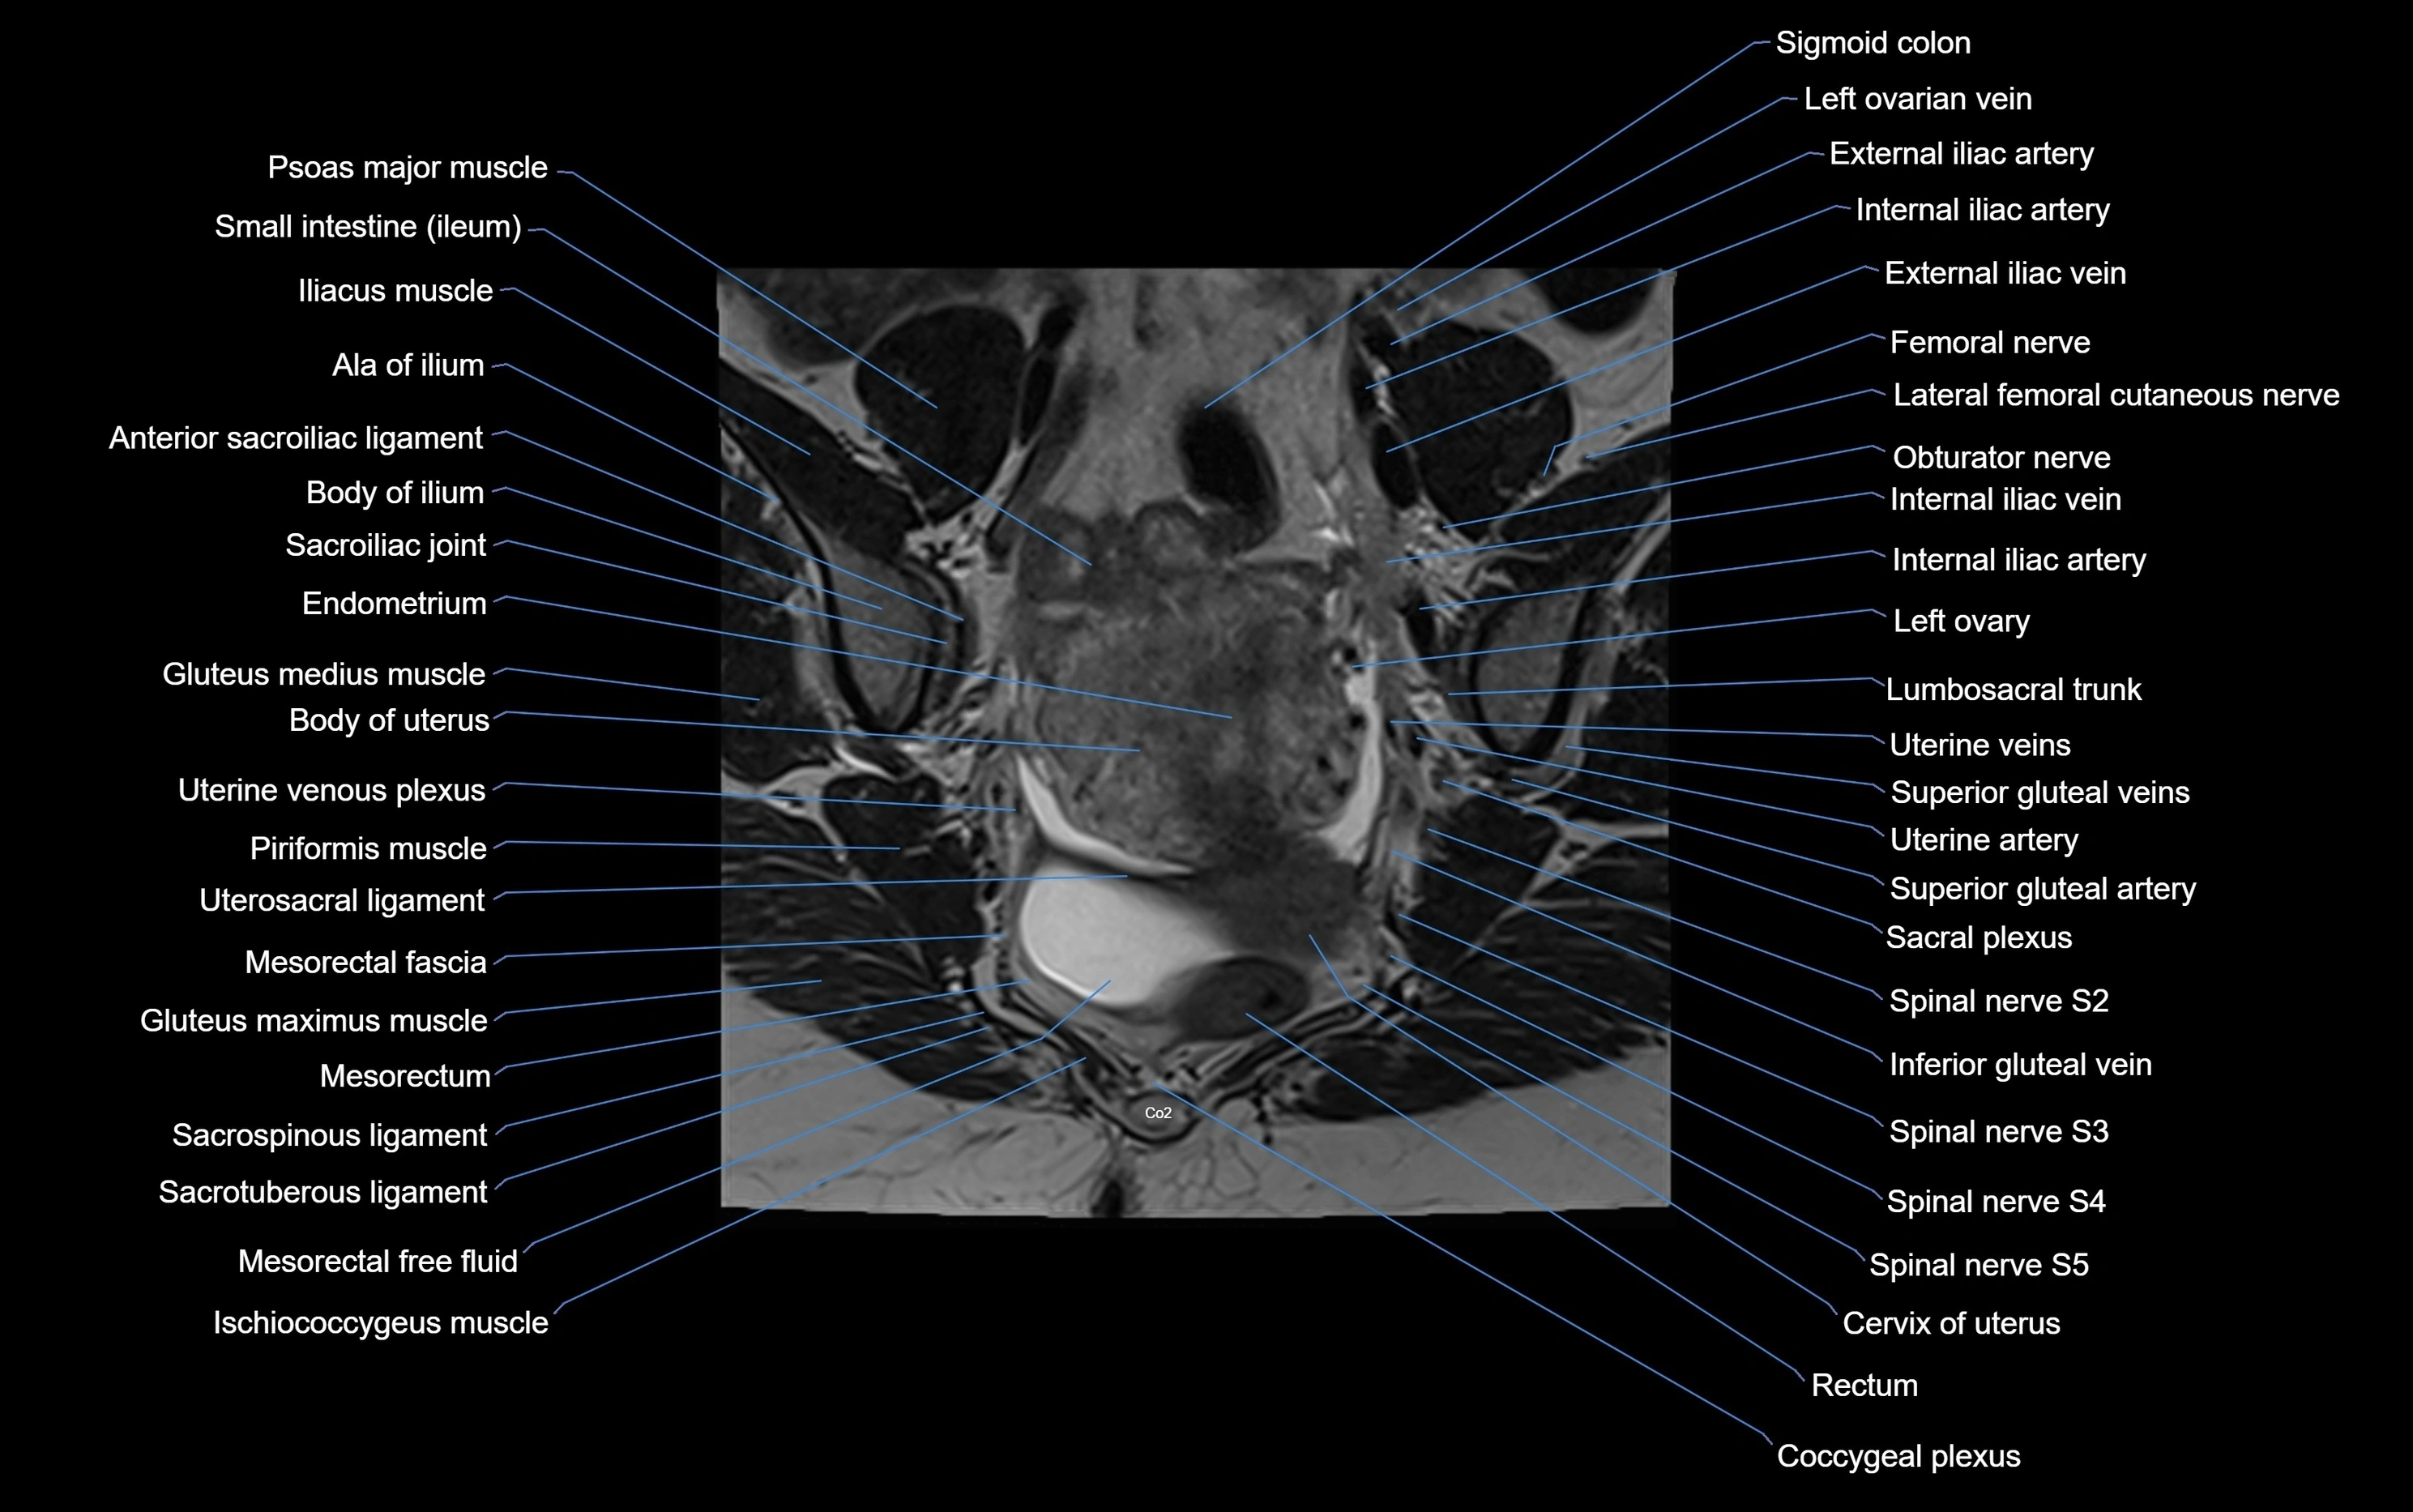

MRI image

image